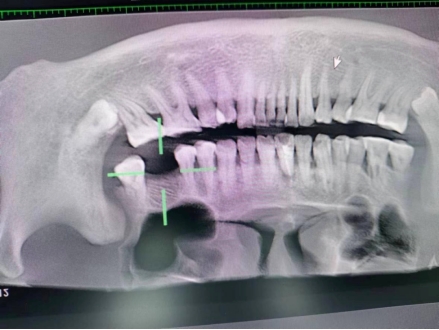

王先生术后检查图

第一台手术结束后,预约已久的王先生也在下午进行种植牙手术,据了解,在朋友的推荐下,王先生已提前完成各项检查等待手术,种植手术结束后,王先生说:“伤口没什么不适感觉,也没有感觉肿胀疼痛”。